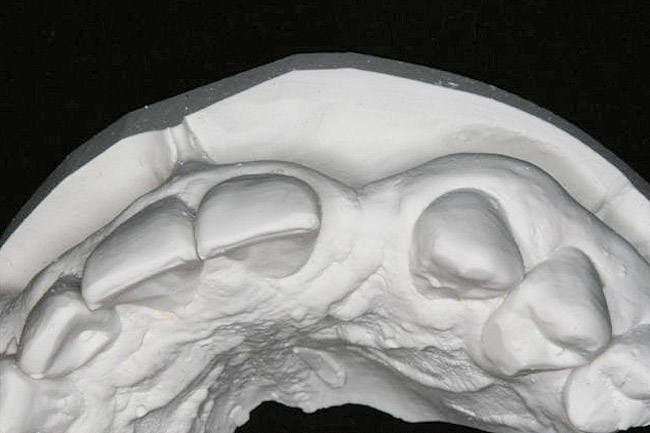

Figure 13   Exploiting study casts for planning single-tooth implant placement and restoration: Mounted study casts permit an estimation of available bone volume (Fig 13); measure the bound edentulous space inter-tooth dimensions (Fig 14); measure the available inter-arch dimension (restorative space) (Fig 15); and evaluate alveolar ridge/tooth relationships (distance from zenith represented by plastic stent to ridge crest) (Fig 16).

Figure 13

The exploration of this architecture is only fully achieved by evaluation of study casts that clearly reveal the detailed anatomy of the alveolus and the peri-coronal tissues. Study casts should be mounted in maximum intercuspal position for the complete treatment planning of single-tooth dental implants. Mounted casts enable estimation of the required 6 mm of space between the ridge crest (approximately 2 mm submucosal) and the opposing tooth and measurement of the mesiodistal interdental distance. The orientation of the implant in the alveolus should neither interfere with the required occlusion nor should it obviate the placement of an esthetic crown (eg, excessively buccal orientation). This can be revealed through the diagnostic waxing process. Encroachment of opposing teeth into the bound edentulous space may suggest the need for possible adjustment or orthodontic movement of the antagonist. When excellent study casts are mounted, it is possible to: estimate bone volume; measure bound edentulous space inter-tooth dimensions; measure inter-arch dimensions; and evaluate alveolar ridge/tooth relationships (superseding resorbed ridge classification) (Figure 13 through Figure 16).